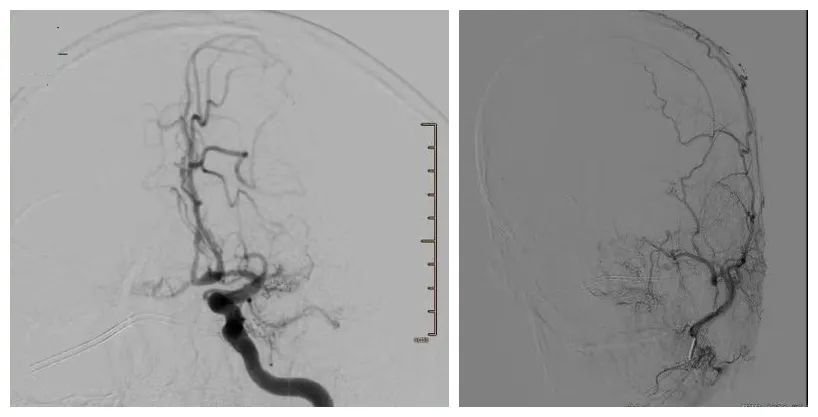

病情复杂,神经外科刘文超副主任医师参加了对李哥的会诊。专家仔细阅读了患者的脑血管造影图片,发现双侧颈内动脉末端均有典型的闭塞表现,颅底有弥漫性的烟雾样新生血管,结合患者的症状和头颅血管CT灌注成像结果进一步明确了“ 缺血型烟雾病” 的诊断。

李哥脑部的供血显示

潘剑威主任医师团队综合评估后发现,李哥左侧额颞叶缺血最为严重,而这个部位也是 负责说话和右侧手脚活动的大脑最主要功能区 ,于是潘剑威主任医师为患者制定了符合他的个性化手术方案:左侧大脑半球直接搭桥和间接搭桥一起做。其目的在于,通过最优化的治疗路径,让患者颅内血管工作更顺畅,更科学,更安全。

5月下旬,浙大一院神经外科血管组潘剑威和刘文超医生为李哥开展了搭桥手术,用一根比头发丝儿还细的针线把直径仅仅1mm左右的大脑中动脉和颞浅动脉作了端侧吻合,同时还作了颞肌贴附手术,为李哥的脑组织血供提供了双保险。一周后,李哥说话不利索、头晕的情况明显好转。复查发现左侧大脑半球的血流量大大提高了,通过治疗一根细小的脑血管挽救了整个家庭。